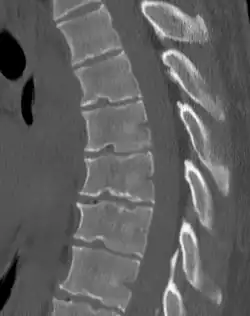

Scheuermann's disease on lateral CT of the T spine

Diagnosis is typically by medical imaging. The degree of kyphosis can be measured by Cobb's angle and sagittal balance.